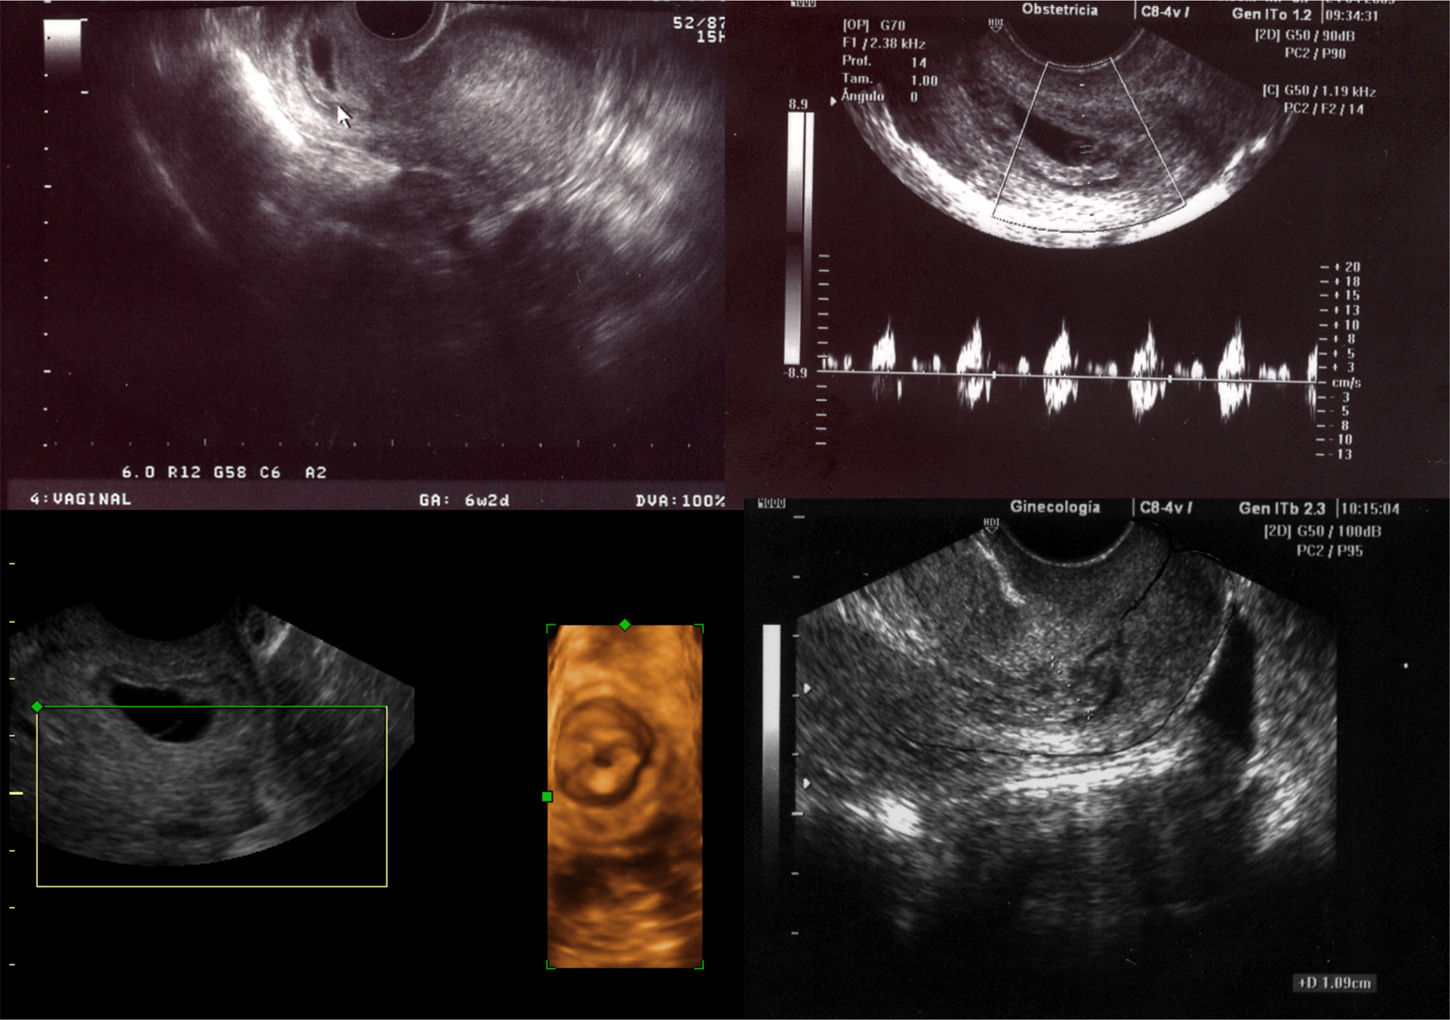

CasosCaso I: Primigesta de 29 años (gestación espontánea) sin antecedentes de interés que consulta a las 6+4 semanas de gestación por metrorragia de 3 días de evolución. En la exploración ginecológica destaca una movilización cervical dolorosa. En la ecografía vaginal se observa una cavidad uterina vacía, anejos normales y a nivel del cérvix posterior un saco gestacional de 52×25mm con un embrión en su interior de 32mm con actividad cardiaca (CA) positiva y una intensa vascularización peritrofoblástica en la valoración Doppler. (fig. 1). Presenta una beta gonadotrofina coriónica humana (B-hGC) de 9.202mU/ml. Se llega al diagnóstico de una gestación extrauterina cervical y se trata con una dosis intramuscular (IM) de 75mg de metotrexate. Al segundo día postratamiento se observa la expulsión del saco gestacional y a los 4 días posmetotrexate el nivel de B-hCG es de 1.636mU/ml. Se observa una evolución favorable con nivel negativo B-hCG (4,5mU/ml) a los 20 días postratamiento (fig. 2).

En 1911 Rubin8 describe los criterios anatomopatológicos del embarazo cervical, pero estos han perdido relevancia ya que el diagnóstico en la actualidad es ecográfico. Hofmann sugiere como criterios diagnósticos ecográficos del embarazo cervical9: la no evidencia de gestación intrauterina y la presencia de un saco gestacional con material trofoblástico a nivel cervical, dando una forma más esférica al cérvix con la presencia de un orificio cervical interior cerrado; describiendo una figura del reloj de arena entre un útero vacío un orificio cervical interior cerrado con un cérvix ocupado.

Jurkovic10, con ecografía en modo-B y Doppler color, propone como criterios diagnósticos: una cavidad uterina vacía con un endometrio engrosado, una dilatación y/o alargamiento del cérvix con una bolsa gestational o material trofoblástico debajo del nivel inferior del orificio cervical interno con ausencia del «Sliding sign» y una identificación de vascularización peritrofoblástica en el examen Doppler.